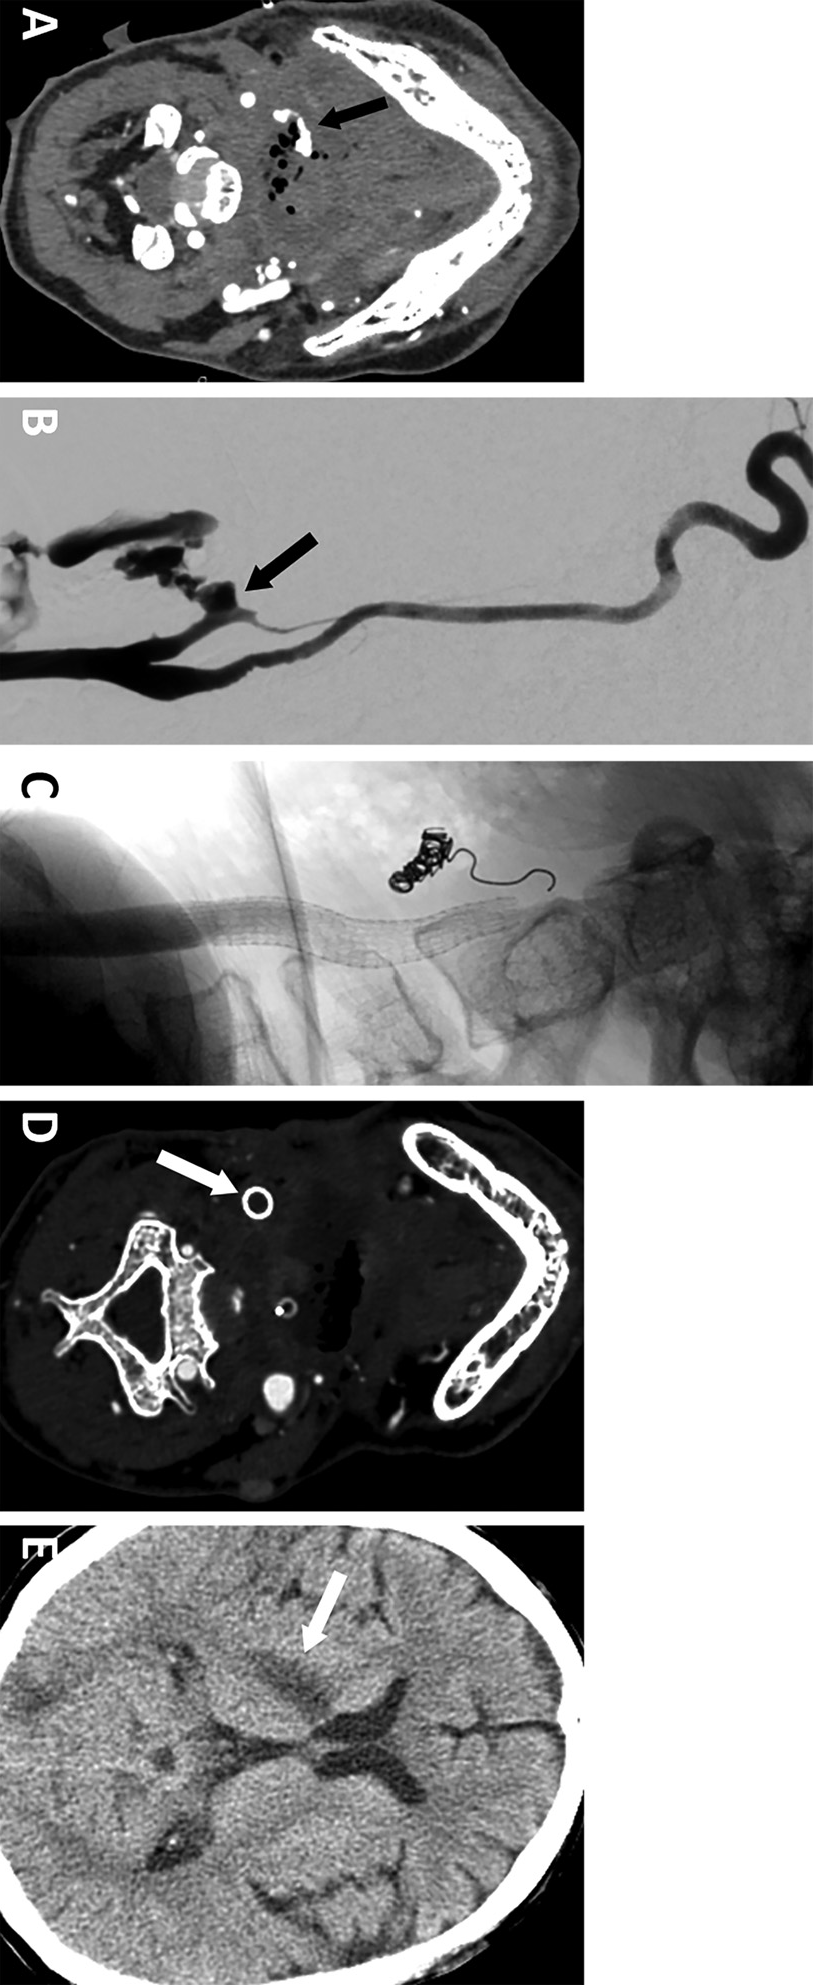

示例三. A,一名49岁口咽癌男性患者,全喉切除术、气管造口术及甲状腺切除术后。末次化疗后出现大量口腔出血伴低血容量性休克。CTA显示右侧面动脉活动性造影剂外渗,伴周围含气坏死组织(箭头所示)。B,血管造影显示右侧面动脉残端活动性造影剂外渗(箭头所示)。C,经覆膜支架植入术处理颈总动脉-颈内动脉,并行右侧颈外动脉圈陷术(采用可推入弹簧圈)后状态。D、E,术后2周颅脑CTA检查,显示覆膜支架内血栓形成及右侧大脑新发梗死灶(箭头所示):